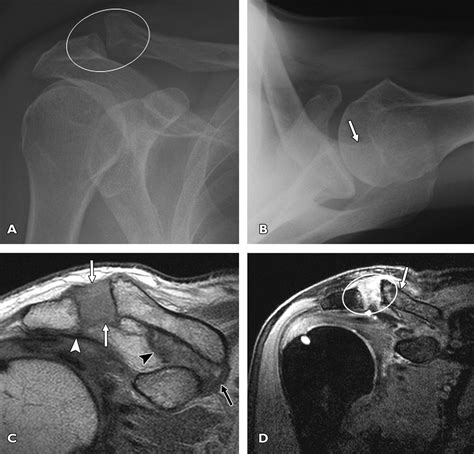

To grasp what happens during an Ac Tendon Injury, it helps to visualize where the injury occurs. The acromioclavicular joint is located at the top of the shoulder where the clavicle (collarbone) meets the acromion (a projection of the shoulder blade). These two bones are held together by a complex set of ligaments, specifically the AC ligaments and the coracoclavicular (CC) ligaments.

When you suffer an injury here, it is technically a ligamentous sprain or tear, but it is frequently categorized alongside tendon issues because of the stress placed on the surrounding musculature. Force applied to the shoulder, such as a direct blow or landing on an outstretched arm, can stretch or tear these stabilizing structures, leading to varying degrees of joint separation.

Medical professionals classify these injuries based on the extent of the ligament damage. This classification system, known as the Rockwood classification, helps determine whether a patient needs conservative treatment or surgical intervention.

Grade III Complete tear of AC and CC ligaments; visible bump. Usually non-surgical, but varies by patient need.

Grade IV-VI Severe displacement of the clavicle. Often requires surgical stabilization.

• A visible deformity or bump on top of the shoulder where the collarbone protrudes.

⚠️ Note: If you hear a loud "pop" during the injury or notice the collarbone moving abnormally, seek professional medical imaging immediately to rule out fractures.